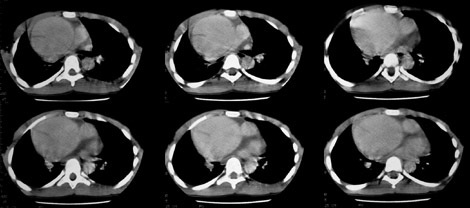

TC: La TC tradizionale è la tecnica più sensibile nell’individuazione di lesioni con componenti calcifiche.

Il suo limite, in passato, era determinato dall’impossibilità di distinguere i falsi aneurismi da quelli veri, e tale ostacolo è stato superato dall’introduzione dell’ANGIO-TC in cui si utilizza un mezzo di contrasto.

Le immagini TC forniscono informazioni dettagliate sulla sede, morfologia, dimensioni dell’aneurisma, sull’eventuale presenza di calcificazioni e trombi endoaneurismatici.

Permettono inoltre di cogliere i rapporti tra la sacca aneurismatica e le strutture anatomiche ad essa contigue oltre che, in caso di rottura, la sede dello stravaso ematico.

La TC spirale riesce ad ottenere una visione panoramica angiografica multiplanare o tridimensionale dell’aorta e delle arterie iliache e ciò permette una valutazione più precisa del diametro dell’aneurisma.